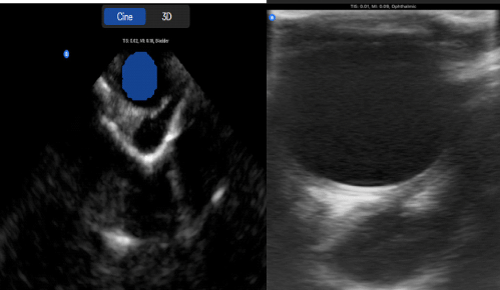

The goal of 3D imaging is to reconstruct the orbit into a three-dimensional image using multiple two-dimensional B-scans. While it is difficult to understand what every image represents when piecing the two-dimensional B-scan pictures to reconstruct the eye and orbit in 3 dimensions, there are several approaches and individual methods to the examination, the secret to which is to make sure there is an organized, repeatable approach to evaluating the complete orbit and globe (Figure 2).

Figure 2: Large Orbital Mass with delineation and 3D configuration extended to extraconal space using Butterfly IQ+ Handhold Ultrasound. (Same lesion shown in B scan for comparison).